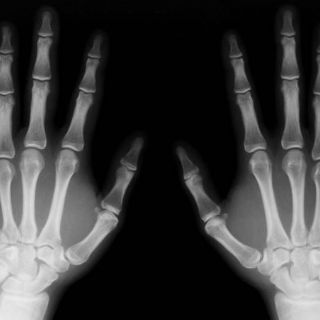

LONDRES, INGLATERRA (05/MAR/2012).- Los suplementos de vitamina E podrían perjudicar al mantenimiento de los huesos, según un estudio realizado por científicos japoneses que recoge hoy la revista británica "Nature Medicine".

La cantidad de masa ósea está determinada por el equilibrio entre dos tipos de células: los osteoblastos, que intervienen en la creación del nuevo tejido óseo, y los osteoclastos, que lo degradan.

En la investigación japonesa, los ratones con dosis altas de vitamina E perdieron masa ósea, un dato que los científicos consideran que se debe a que este componente aumenta el número de osteoclastos, lo que a su vez se traduce en que se destruye más hueso del que se crea.

Los investigadores subrayaron que, aunque estos resultados podrían ser importantes para prevenir el riesgo de fracturas en un futuro, es necesaria una investigación más profunda en humanos.